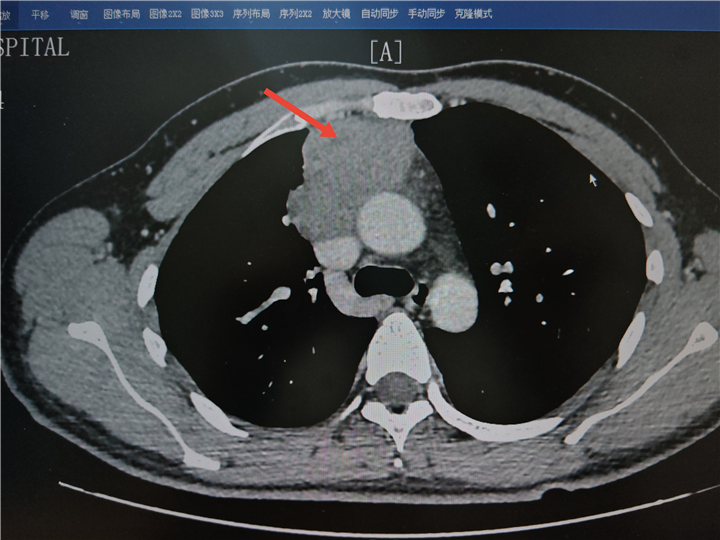

该患者因意外摔倒查出纵隔内有近 7 cm 的巨大肿瘤,此肿瘤不仅体积庞大,还侵犯了无名静脉和上腔静脉。传统观点视这类血管受侵的偏晚期纵隔肿瘤为「手术禁区」,患者因手术风险高而求治无果,后来我院。

面对难题,胸外一科丁翔副主任团队联合多科室专家开展多学科会诊(MDT)。三维重建影像显示,肿瘤虽侵犯重要静脉系统,但主动脉等核心动脉未受累。丁翔副主任表示,这是根治性手术的最后一个机会窗口,不过手术需跨越三大难关: